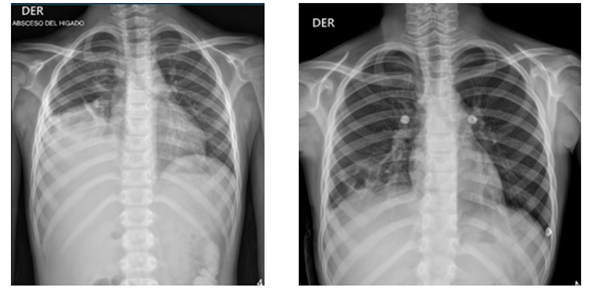

Niño de 8 años de edad, procedente de San Marcos, Sucre, sin antecedentes de relevancia, ingresa a urgencias de HINFP remitido porque presenta un cuadro clínico de 20 días de evolución consistente en fiebre, dolor en hipocondrio derecho y hepatomegalia. Se encuentra sin alteración de estado general y signos vitales en límites normales. En paraclínicos iniciales se evidencia marcada leucocitosis (>25.000 cel/mm3) con desviación a la izquierda, reactantes de fase aguda elevados (proteína C reactiva, velocidad de sedimentación globular), función renal y hepática conservada, hemocultivos por 2 sin desarrollo. Se realizan estudios de imágenes que incluyen ecografía de abdomen total y TAC de abdomen que reportan hígado de ecotextura heterogénea por la presencia de una lesión hipoecoica, de contornos irregulares, que compromete los segmentos II, III y IV, sin flujo al análisis Doppler color, que mide 90 x 58 x 58 mm, para un volumen estimado de 162 cc e hígado aumentado de tamaño por presencia de lesión focal, hipodensa, en rango de densidad líquida no acuosa de 8 x 6 cm, en segmento 8 (Figura 1), respectivamente. Se establece el diagnóstico de absceso hepático piógeno vs amebiano. El paciente había iniciado tratamiento antibiótico con trimetoprima-sulfametoxazol y meropenem cuatro días antes del ingreso, régimen que se suspendió al llegar al HINFP y en su lugar se inició ceftriaxona y metronidazol, además, se indica valoración multidisciplinaria: infectología pediátrica, gastroenterología pediátrica, radiología intervencionista, cirugía pediátrica. Al día siguiente el paciente presenta tos irritativa, sin deterioro de su estado general, se indica manejo antihistamínico. Por persistencia de síntomas y abolición de murmullo vesicular en hemitórax derecho a los tres días del ingreso al hospital se realiza radiografía de tórax (Figura 2), con reporte de ocupación parcial del hemitórax derecho en sus dos tercios inferiores asociado a borramiento de los ángulos costo y cardiofrénicos ipsilaterales sugestivo de derrame pleural. Se deriva a unidad de cuidados intensivos por riesgo de falla ventilatoria, y al día siguiente es drenado 20 cc de material purulento del hígado por parte de radiología intervencionista, con fijación de drenaje cerrado con posterior retiro cuatro días después por ausencia de secreción. Se realizan estudios microbiológicos de la secreción, incluyendo prueba de Gram y cultivo, sin aislamiento de microorganismos. Pasados dos días desde el drenaje de absceso hepático, por parte de cirugía pediátrica se drena 20 cc de material purulento de hemitórax derecho y decorticación, se fija tubo de tórax con posterior retiro cuatro días después por ausencia de secreción. Se reporta adenosina desaminasa (ADA) en líquido pleural negativa, cultivo para Mycobacterium líquido pleural negativo, cultivo líquido pleural (tres muestras) negativo, panel de neumonía en líquido pleural negativo, citoquímico de líquido pleural tipo exudado. El paciente evoluciona satisfactoriamente y egresó luego de dos semanas hospitalizado, culminando 14 días de manejo intravenoso con antibiótico (ceftriaxona y metronidazol) y seguimiento por parte de equipo multidisciplinario.

El AHA puede complicarse por contigüidad con inflamación de la serosa pleural y perforación del absceso hacia el tórax y pericardio, exhibiendo compromiso pleural en el 14% y pericarditis en el 40%, aunque sigue siendo más frecuente la apertura del AH al diafragma y parénquima pulmonar, seguramente porque la localización más frecuente del AH es el lóbulo derecho, esto explicado desde los términos de anatomía y mayor irrigación sanguínea3,15. La localización izquierda predispone a complicaciones como roturas y las lesiones múltiples se asocian al doble de mortalidad que las lesiones únicas6. En el caso presentado, la complicación descrita fue pleural con consiguiente inflamación y perforación del absceso hacia hemitórax derecho. Clínicamente estas complicaciones pueden presentarse con tos y dolor pleurítico e incluso con tos hemoptoica o con expectoración rojiza, como “pasta de anchoas”, secundario a la estasis de líquido producto de la licuefacción del proceso inflamatorio, llegando a desarrollarse empiema. Está indicada la realización de radiografía de tórax en caso de sospecha de complicaciones, ya que puede observarse elevación del hemidiafragma derecho o derrame pleural3. En nuestro caso, el paciente solo presentó tos seca, sin expectoración, sin compromiso del estado general, a pesar del gran compromiso del hemitórax derecho. Otras complicaciones incluyen peritonitis, ascitis, síndrome de Budd-Chiari, ruptura o efusión pericárdica5,21.